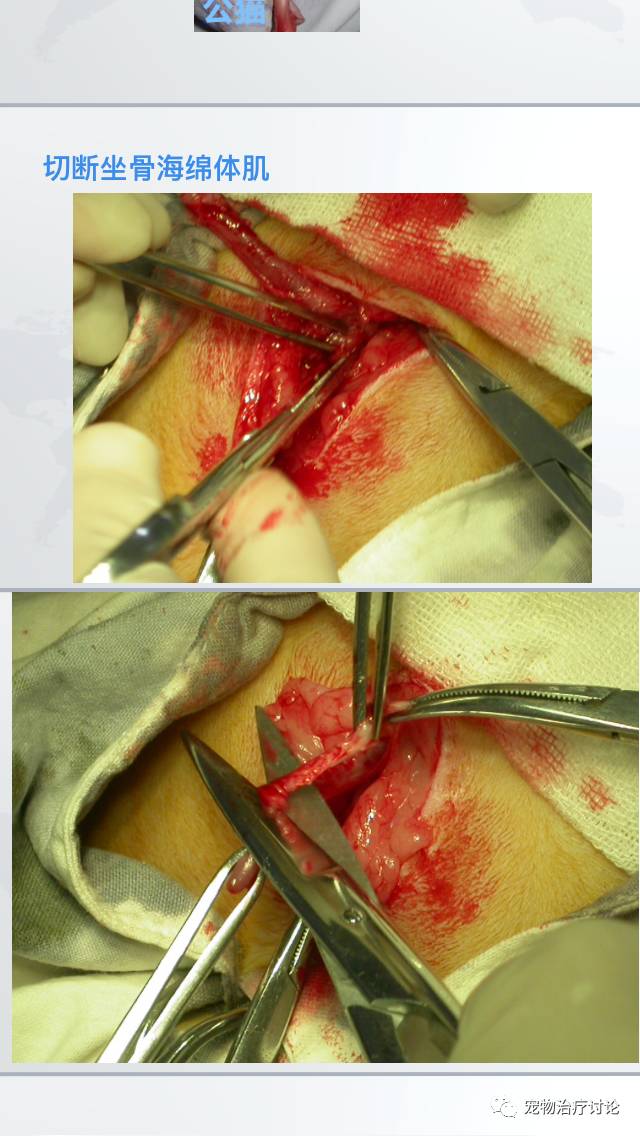

㈡手术疗法--尿道造口术

分离肌肉

缝合尿道

对于通过插导尿管不能疏通及治愈的FLUTD、反复发作的FLUTD,尿道早口术是最终的解决办法。(具体手术方法,见外科手术)